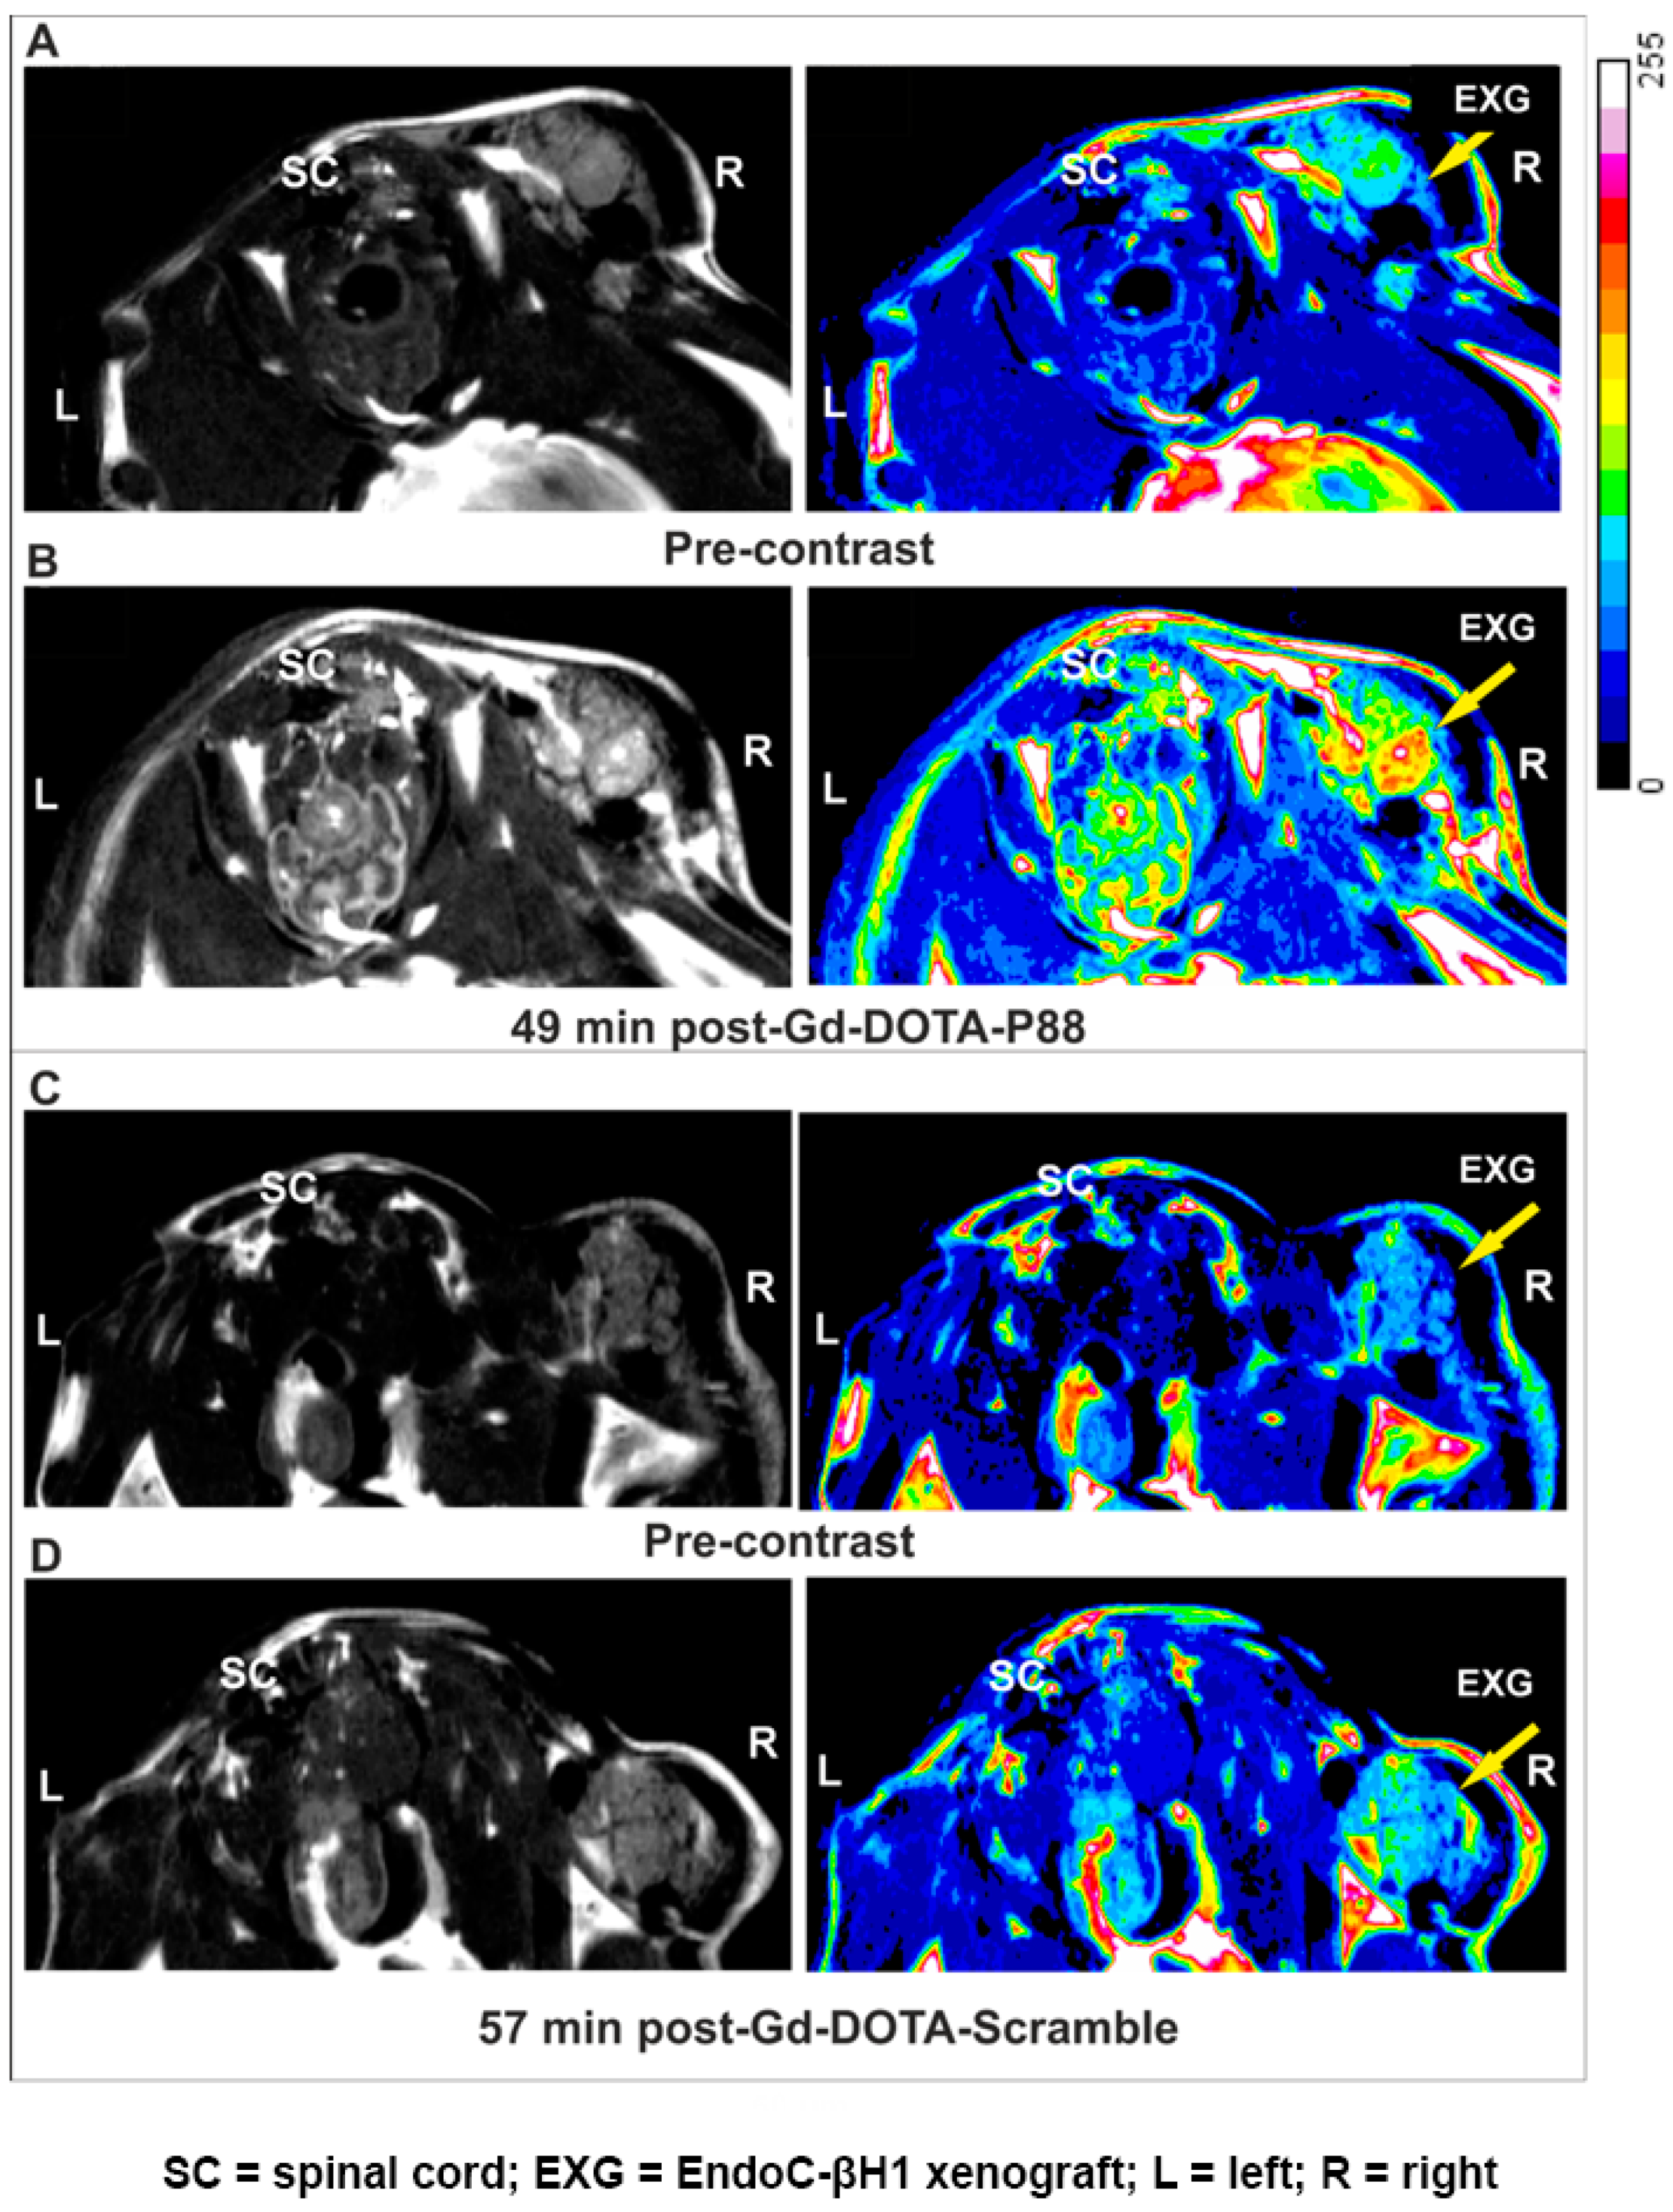

Molecules Free Full Text Imaging Of Human Insulin Secreting Cells With Gd Dota P A Paramagnetic Contrast Agent Targeting The Beta Cell Biomarker Fxyd2ga Html